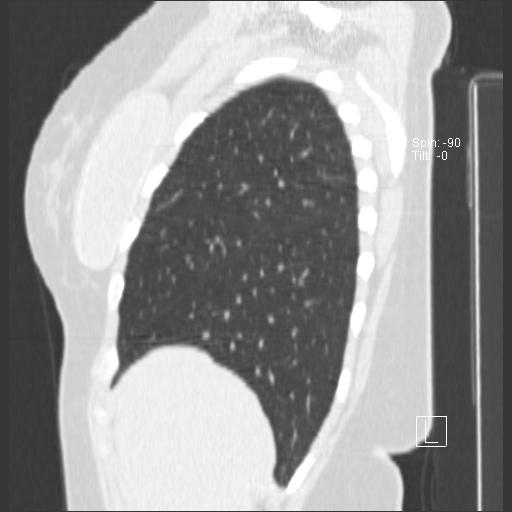

New CT images (without contrast) for 40 year old female with silicone breast implants. Formal diagnosis is expected soon. Images from 2010 can be seen here http://radiology-images.blogspot.com/p/40-year-old-female-silicone-implants.html